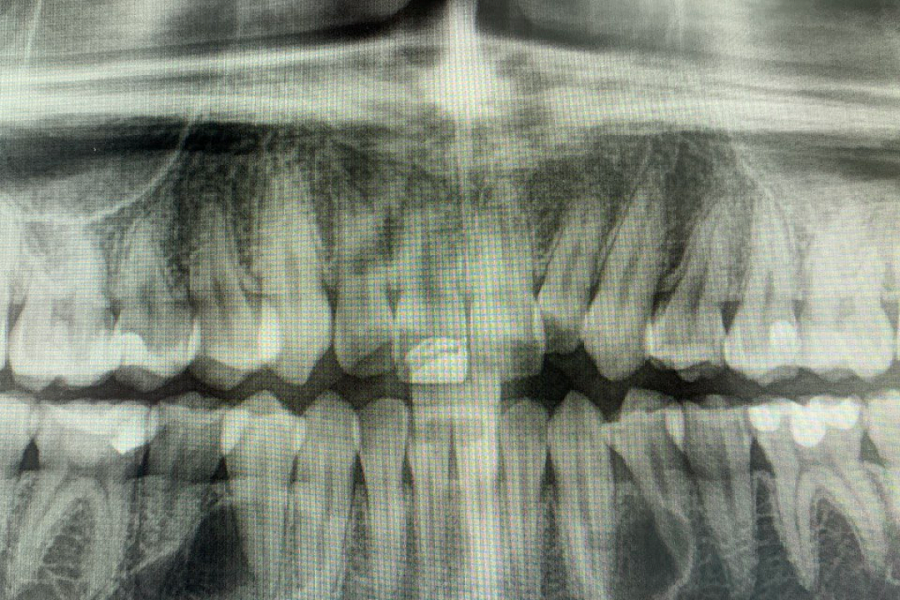

Пациент направлен врачом-ортодонтом с целью удаления ретинированных дистопированных зубов. У пациента аномалия: лишние зубы в передне-боковых отделах.

Зубы были удалены через окошко в кости, сделанное изнутри полости рта со стороны языка. Заживление прошло отлично, пациент ни на что не жалуется, соседние зубы не были повреждены.